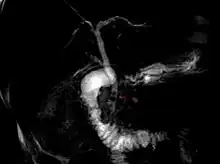

Coledocolitíase

Coledocolitíase é a presença de cálculos no ducto colédoco. Esta condição causa icterícia e lesão às células do fígado, sendo uma emergência médica, necessitando de CPRE ou tratamento cirúrgico.